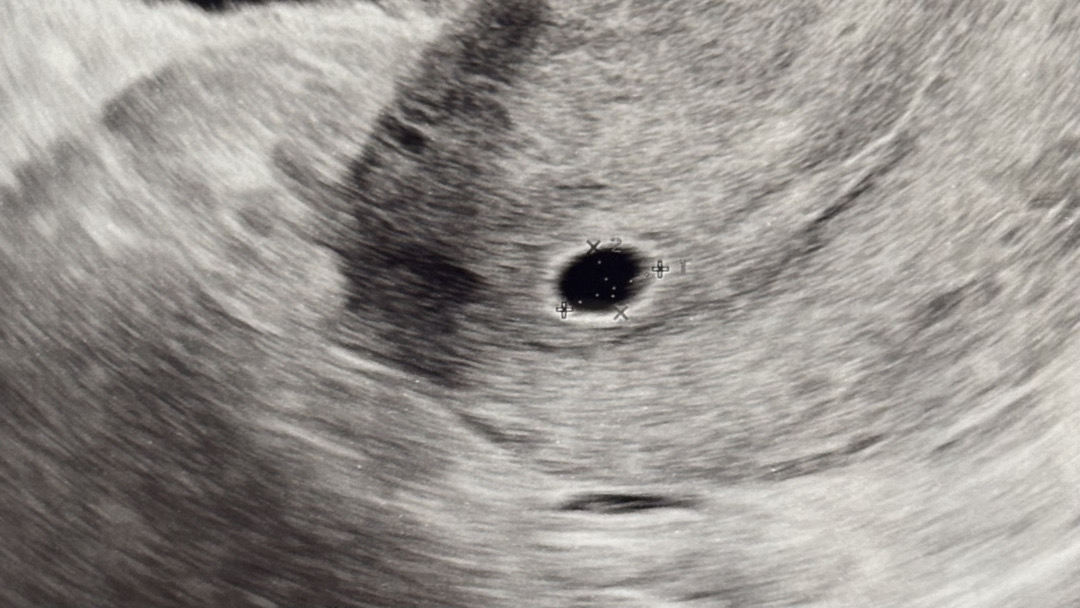

마지막 생리일은 5월 4일인데 제가 생리주기가 35-36일 정도긴 해요ㅜㅜ 6월 10일 산부인과 갔을때 아기집 0.28mm라고 하셔서 너무 작아서 사실 아기집 추정이라고 하셨거든요! 6월 17일에 오라했는데 좀더 기다렸다가 오늘 19일 다녀왔어요.. 근데 아기집이 0.79mm고 난황이 보여야할 시기인데 안보인다고 고개를 갸우뚱 하시기도 하고.. 사실 1cm이상으로 아기집이 컸어야 하는데 성장도 느리다고 하시더라구요.. 막생기준으로 6주6일인데 배란일 기준으로는 5주 4일 정도 된거 같은데 일주일 뒤에 가면 난황 잘 볼 수 있겠죠,,? 너무너무 무섭고 겁나고 진료 받고 나오자마자 눈물이 나더라구요.. 내가 너무 열심히 일했나 싶고ㅠㅠ 잠도 안자고.. 어제부터 베이지색? 갈색냉 같은게 계속 묻어나왔는데 .. 저같은 분 계신가요? ㅜㅜ 사진은 오늘 보고 온 아기집입니댜..!